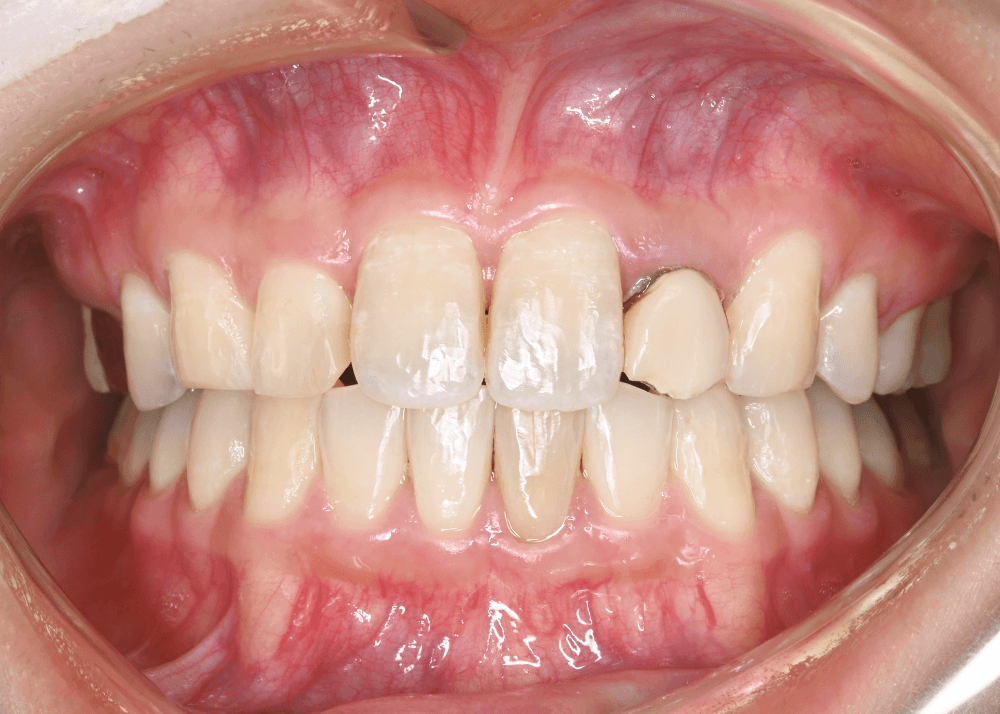

治療後の変化

治療後は、舌側に倒れていた前歯の傾きが改善しています。

前歯のポジションが適正化されたことで、スマイル時に奥まって見えていた歯の見え方が改善し、より自然な印象になっています。

また、唇を内側から支える「口唇サポート」が回復し、横顔の印象にも変化がみられました。

治療前後の写真比較

治療前

治療後(32か月)